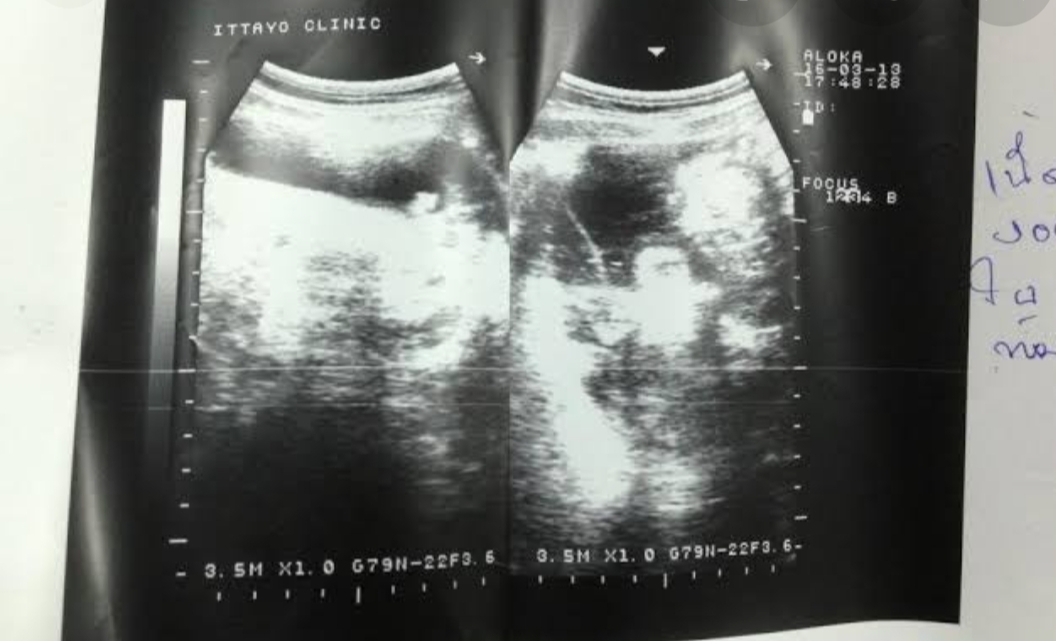

ไปตรวจมาพบเนื้องอกิปีกมดลูกซ้าย

การเป็นเนื้องอกอันตรายไหม กลัวมากตอนนี้